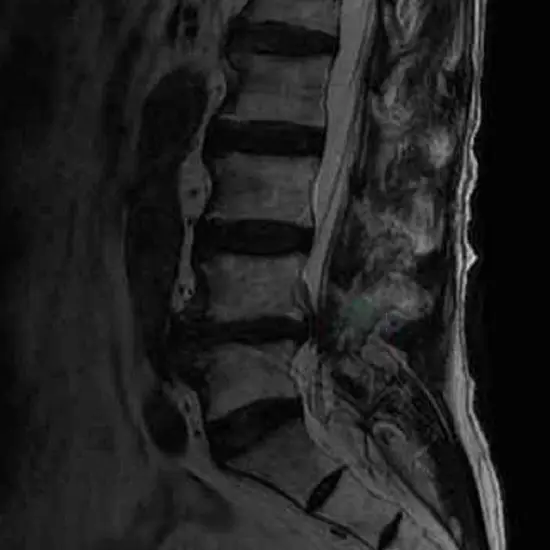

What is MRI Myelography?

Myelography is an imaging test that involves putting a spinal needle into the spinal canal and injecting contrast material into the subarachnoid space. This is done to get a clear picture of the spinal cord, nerve roots, subarachnoid area, and spinal column.

Why is MRI Myelography done?

Myelography detects abnormalities in the spinal cord, spinal canal, spinal nerve roots, and spinal cord blood vessels.

MRI (Magnetic Resonance Imaging) screening of the spinal cord is a non-invasive radiology test used to evaluate the condition of the spinal cord and surrounding tissue. MRI Myelography is done to look for spinal cord conditions and the surrounding area.